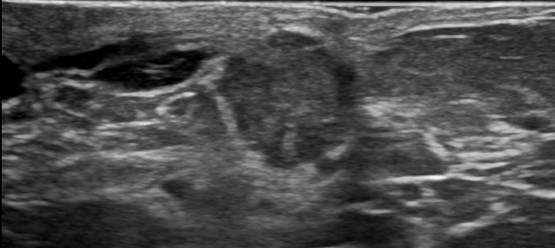

Ung thư vú

Ung thư vú - Ảnh 3

» Thông tin: Nữ giới – 69 tuổi.

» Lâm sàng: Kiểm tra sức khỏe.